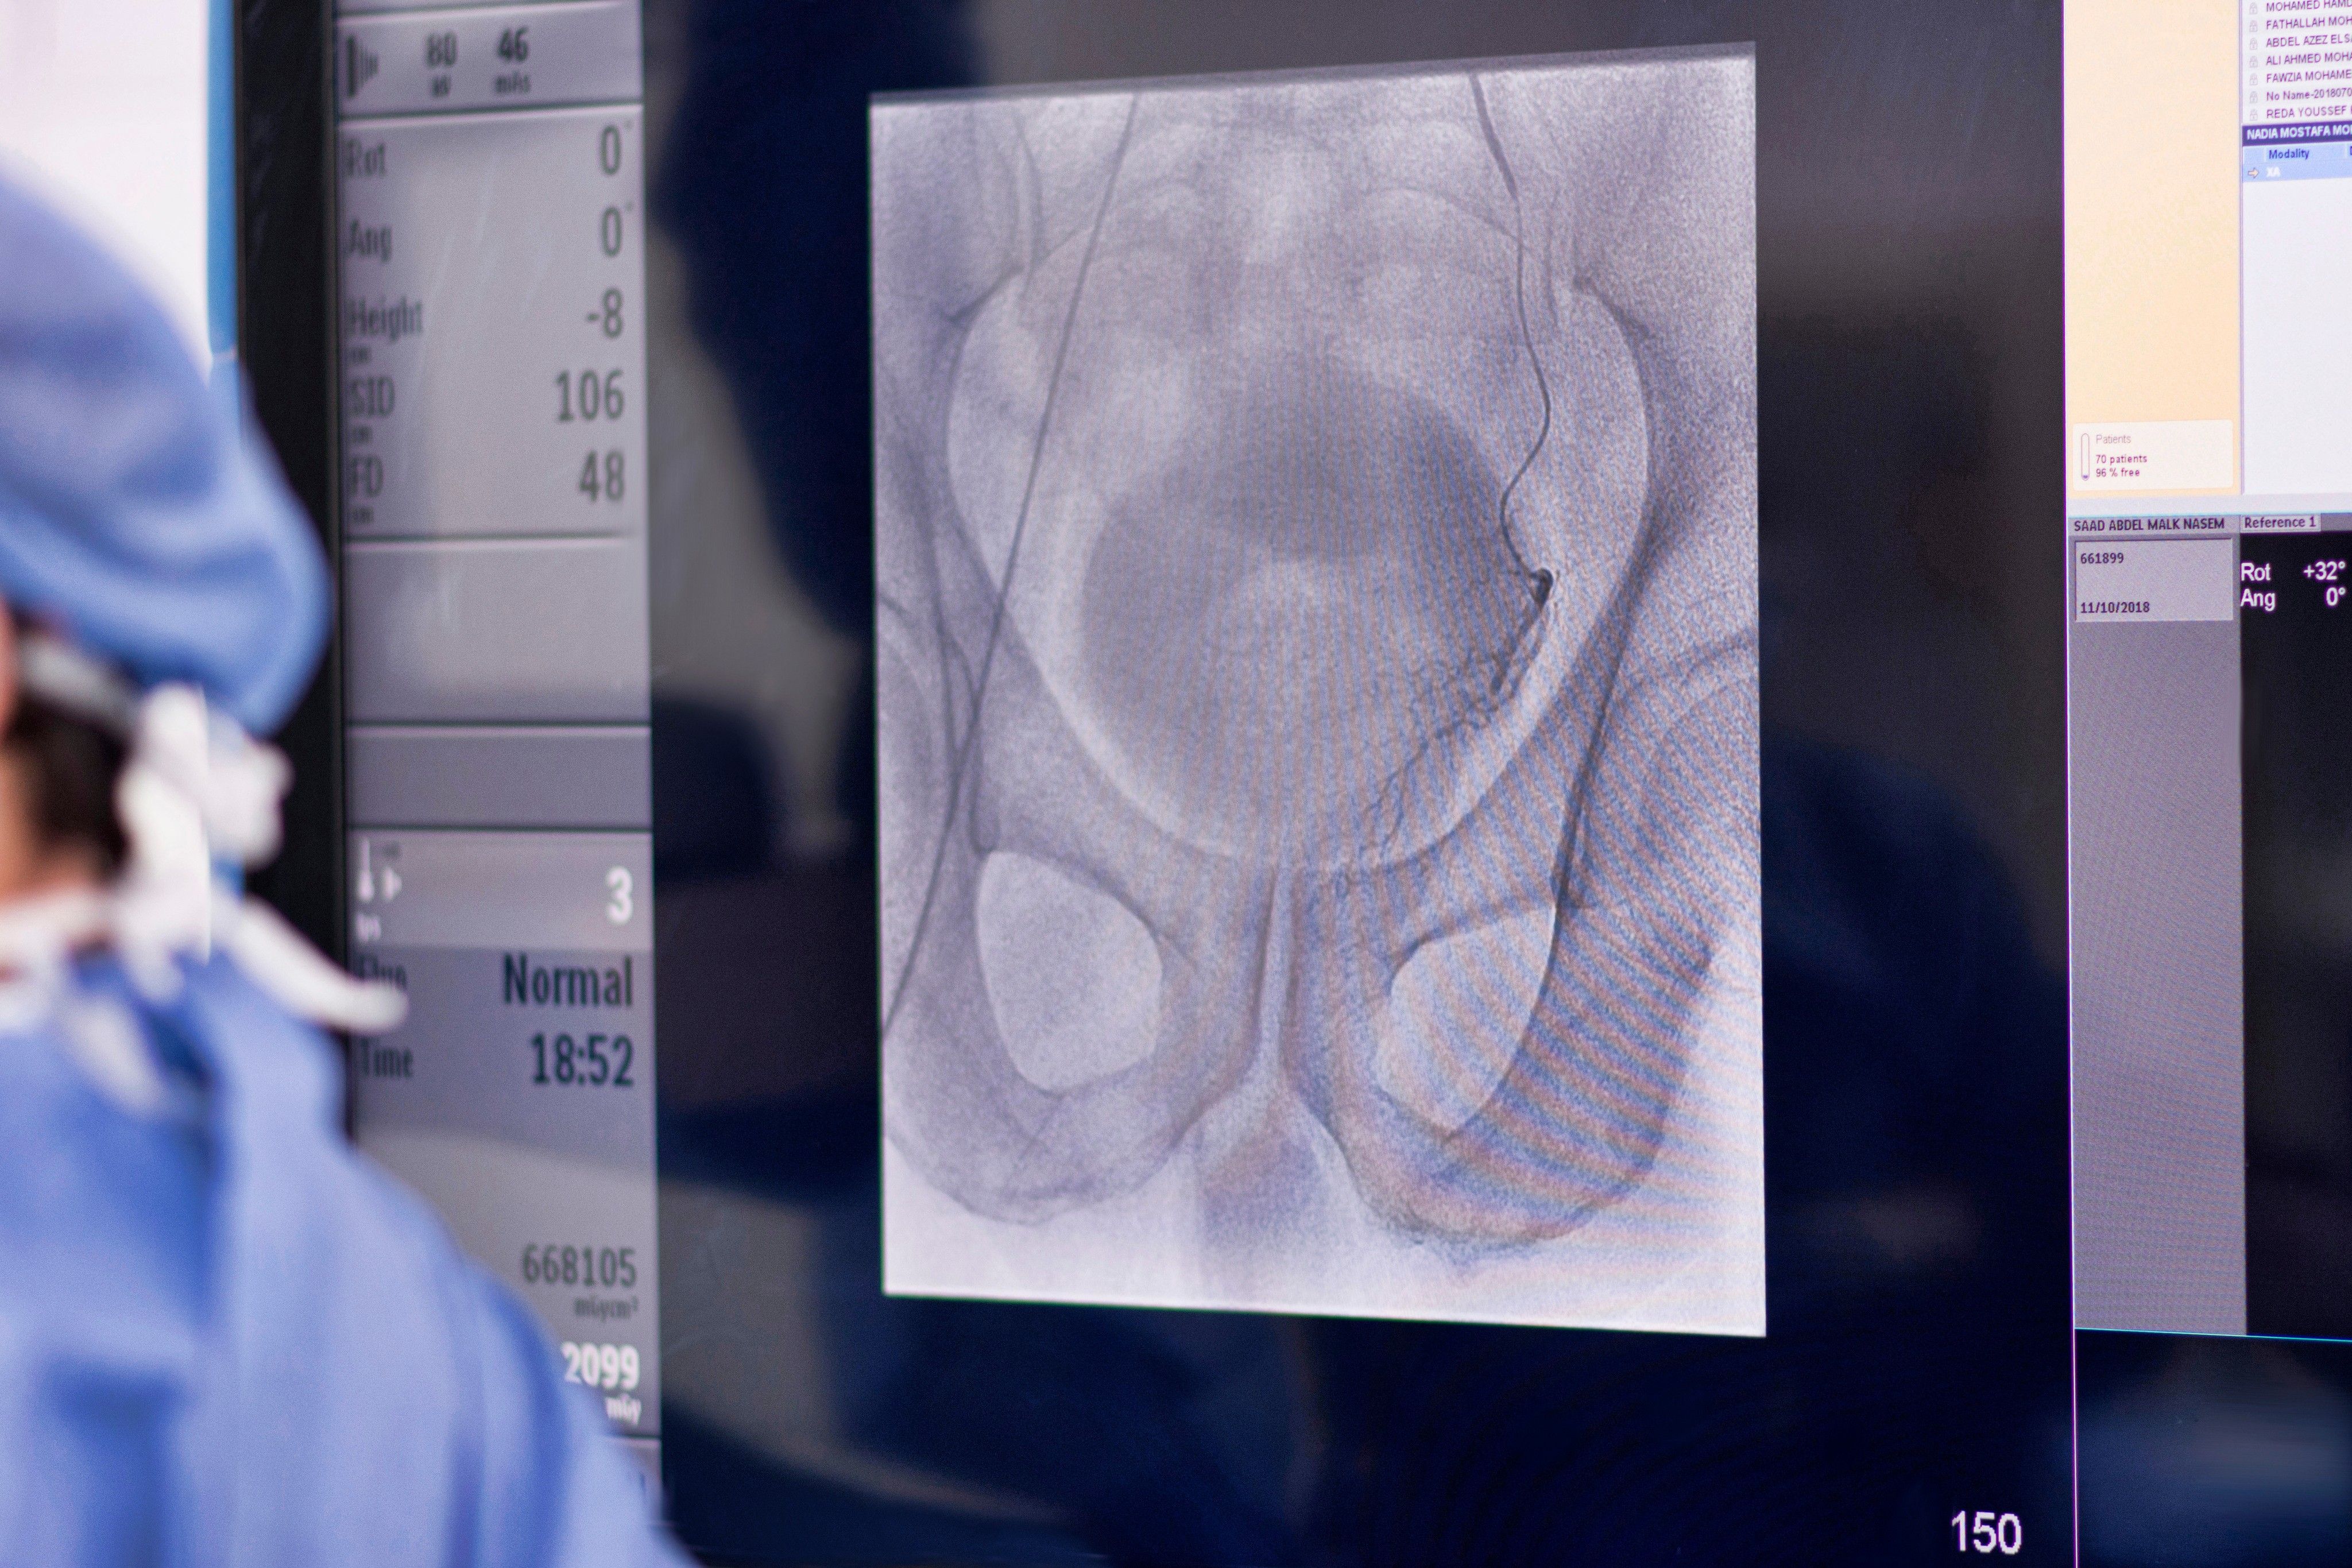

Interventional Radiologist performing Prostatic artery embolization (PAE)

What is Prostate Artery Embolization?

| PR Labs

If you have BPH, prostate artery embolization may be a treatment option you wish to explore. Learn more about the procedure and overall prostate health!